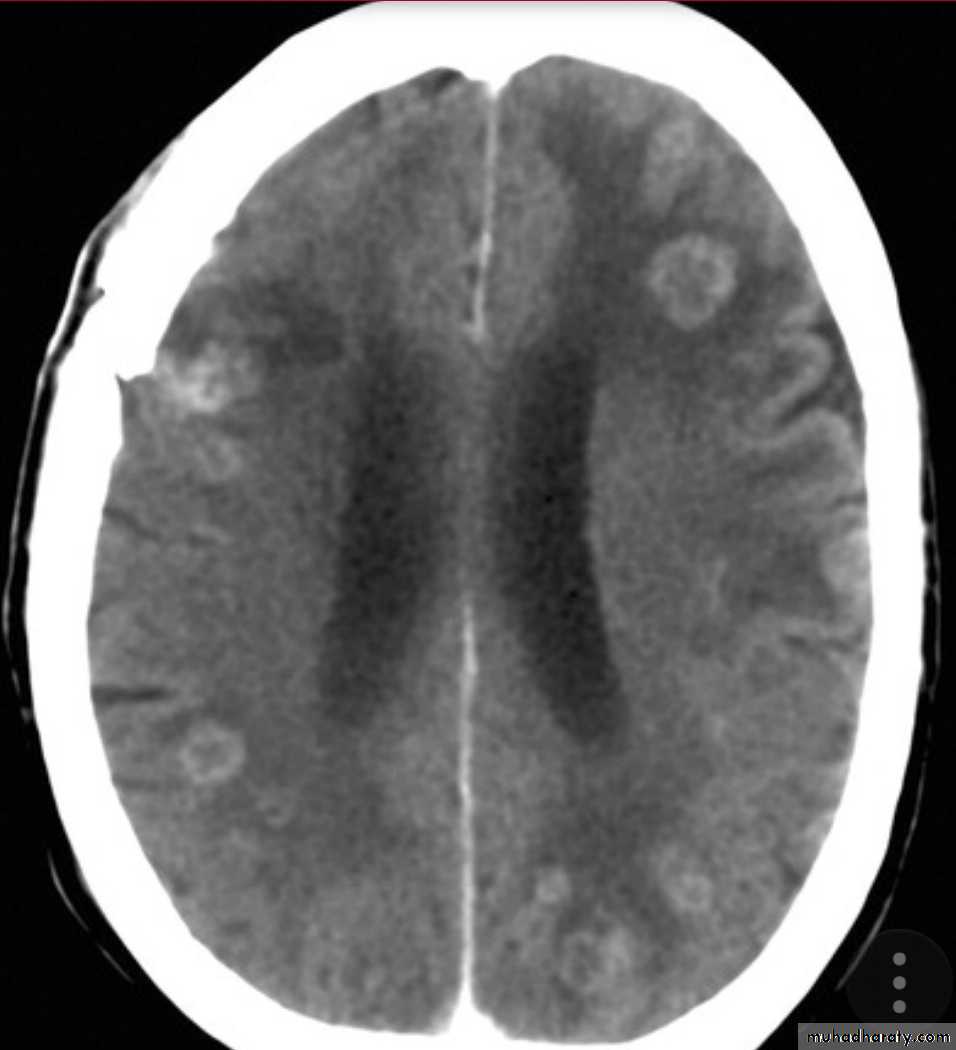

1- Miliary tuberculosis with multiple tubercles in numerous organs & tissues.2- Isolated metastatic organ lesions e.g., in kidney, bone, vertebra, joint & epididymis.

* or enter through the lymphatic channel or blood stream causing Miliary TB. or isolated organ TB.